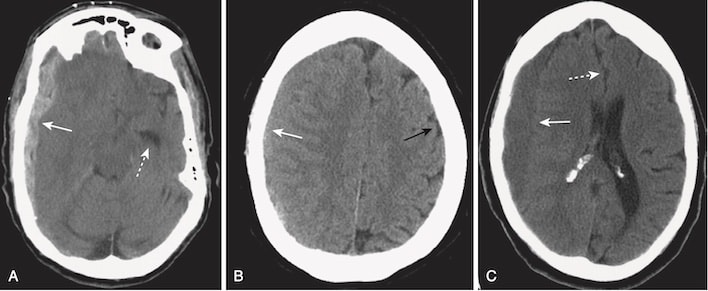

- Một trong hai cơ chế này có thể tạo ra dập não (contusion). Các đụng dập xuất huyết là những xuất huyết, kèm theo phù nề, thường thấy ở phần dưới thùy trán và phần trước thùy thái dương trên hoặc gần bề mặt của não (Hình 10).

- Nhận biết xuất huyết trong não do chấn thương trên CT:

- Đụng dập xuất huyết não có thể xuất hiện dưới dạng nhiều vùng nhỏ, được phân cách rõ ràng với đậm độ cao trong nhu mô não (xem Hình 10, A).

- Chúng có thể được bao quanh bởi một vành giảm tín hiệu (hypodense) do phù nề (xem Hình 10, B).

- Hiệu ứng choán chỗ thường gặp. Hiệu ứng choán chỗ có thể ép các não thất và đẩy lệch não thất thứ 3 và vách ngăn sang bên đối diện. Sự dịch chuyển như vậy có thể gây ra tổn thương não hoặc mạch máu nghiêm trọng.

- Những di lệch này được gọi là thoát vị (herniation). Những bệnh nhân có hiệu ứng choán chỗ đủ lớn có nguy cơ bị thoát vị não qua lều hoặc dưới liềm và tử vong (xem Hình 10, B). Các dạng thoát vị não được mô tả trong Bảng 5.